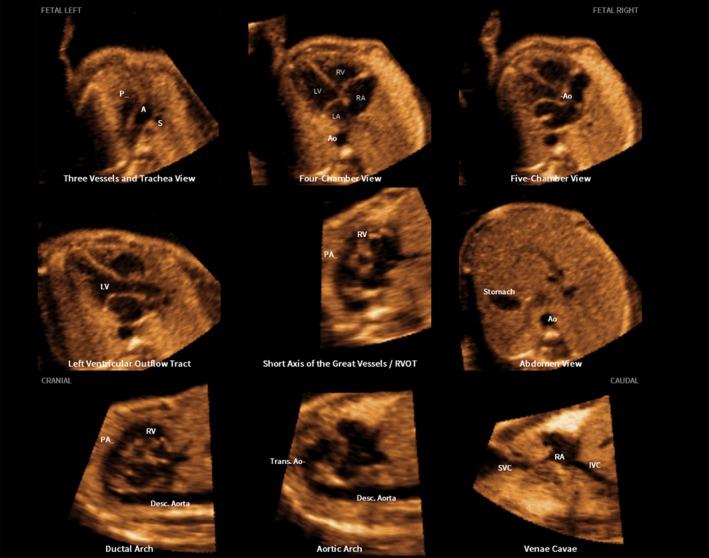

A prospective cohort study was conducted of fetuses in the second and third trimesters with a normal heart or with congenital heart disease (CHD). One or more spatiotemporal image correlation (STIC) volume datasets, combined with color or bidirectional power Doppler (S-flow) imaging, were acquired in the apical four-chamber view. Each successfully obtained STIC volume was evaluated by STICLoop™ to determine its appropriateness before applying the FINE method. Visualization rates for standard fetal echocardiography views using diagnostic planes and/or Virtual Intelligent Sonographer Assistance (VIS-Assistance®) were calculated for grayscale (removal of Doppler signal), color Doppler and S-flow Doppler. In four cases with CHD (one case each of tetralogy of Fallot, hypoplastic left heart and coarctation of the aorta, interrupted inferior vena cava with azygos vein continuation and asplenia, and coarctation of the aorta with tricuspid regurgitation and hydrops), the diagnostic potential of this new technology was presented.

A total of 169 STIC volume datasets of the normal fetal heart (color Doppler, n = 78; S-flow Doppler, n = 91) were obtained from 37 patients. Only a single STIC volume of color Doppler and/or a single volume of S-flow Doppler per patient were analyzed using FINE. Therefore, 60 STIC volumes (color Doppler, n = 27; S-flow Doppler, n = 33) comprised the final study group. Median gestational age at sonographic examination was 23 (interquartile range, 21-27.5) weeks. Color Doppler FINE generated nine fetal echocardiography views (grayscale) using (1) diagnostic planes in 73-100% of cases, (2) VIS-Assistance in 100% of cases, and (3) a combination of diagnostic planes and/or VIS-Assistance in 100% of cases. The rate of generating successfully eight fetal echocardiography views with appropriate color and S-flow Doppler information was 89-100% and 91-100% of cases, respectively, using a combination of diagnostic planes and/or VIS-Assistance. However, the success rate for the ninth echocardiography view (i.e. superior and inferior venae cavae) was 33% and 30% for color and S-flow Doppler, respectively. In all four cases of CHD, color Doppler FINE demonstrated evidence of abnormal fetal cardiac anatomy and/or hemodynamic flow.

CONCLUSIONS

The FINE method applied to STIC volumes of normal fetal hearts acquired with color or bidirectional power Doppler information can generate successfully eight to nine standard fetal echocardiography views (via grayscale, color Doppler or power Doppler) in the second and third trimesters. In cases of CHD, color Doppler FINE demonstrates successfully abnormal anatomy and/or Doppler flow characteristics. Published 2017. This article is a U.S. Government work and is in the public domain in the USA. Ultrasound in Obstetrics & Gynecology published by John Wiley & Sons Ltd on behalf of the International Society of Ultrasound in Obstetrics and Gynecology.